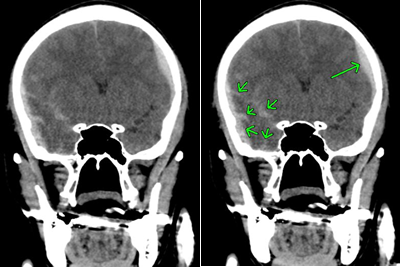

対側損傷の具体例

CTは前頭葉左側部の頭蓋骨骨折と脳挫傷の合併症です。対側損傷が発生し、対角線上の右後頭部に脳挫傷を発症しています。

対側損傷はびまん性軸索損傷を伴うことも多い

対側損傷では中間部位に外力が不均衡に伝わる結果、びまん性軸索損傷を伴うことも多いです。

対側損傷の所見があり、かつ、重度な意識障害のあるときは、びまん性軸索損傷が疑われます。早期に精度の高いMRIでT2スター強調画像を撮影したいところです。